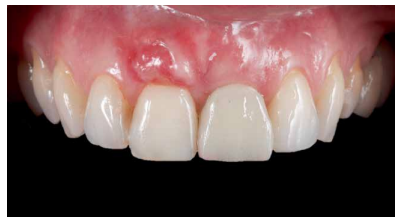

Conclusiones: La rehabilitación sobre implantes en situaciones de pérdida dental en el sector anterior estético y en especial, en pacientes jóvenes, requiere un plan de tratamiento multidisciplinar en cuanto a la extracción del diente y colocación del IOI en la posición tridimensional correcta, existiendo diferentes aspectos a tener en cuenta para ello, especialmente el remanente óseo residual, la posición del margen gingival, así como la preservación y acondicionamiento de los tejidos duros y blandos periimplantarios mediante injertos y un manejo correcto de una prótesis provisional hasta conseguir un perfil de emergencia y contorno gingival ideal antes de la corona definitiva

Conclusions: Rehabilitation on implants in situations of tooth loss in the aesthetic anterior sector, especially in young patients, requires a multidisciplinary treatment plan in relation to tooth extraction and placement of the OII in the correct three-dimensional position. There are various aspects to be taken into account, particularly the residual remaining bone, the position of the gingival margin, as well as the preservation and conditioning of the peri-implant hard and soft tissues by means of grafts and proper handling of a provisional prosthesis until an ideal emergence profile and gingival contour is achieved before the final crown.